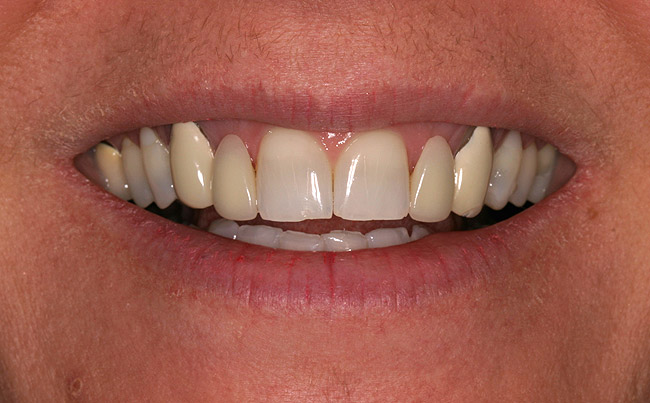

Figure 7c  Completed single all-ceramic screw-retained implant crown site on tooth No. 9, revised porcelain three-quarter laminate veneers for teeth Nos. 8 and 9, cemented with Kerr NX3 Nexus¬Æ Third Generation Dual Cure Resin cement.

Figure 7c

Figure 7d  Completed single all-ceramic screw-retained implant crown site on tooth No. 9, revised porcelain three-quarter laminate veneers for teeth Nos. 8 and 9, cemented with Kerr NX3 Nexus¬Æ Third Generation Dual Cure Resin cement.

Figure 7d

Figure 7e  Completed single all-ceramic screw-retained implant crown site on tooth No. 9, revised porcelain three-quarter laminate veneers for teeth Nos. 8 and 9, cemented with Kerr NX3 Nexus¬Æ Third Generation Dual Cure Resin cement.

Figure 7e

When a patient presents with a missing anterior tooth and heavily treated adjacent teeth, although conceptually an FPD option may seem the most appropriate choice, it can be argued that it would not be the most favorable option. If long-term treatment outcome is a strong motivator for the patient, then a treatment plan that includes individual restored units would be the more appropriate choice. Consequently, the patient would most likely have improved benefit with a single implant-supported restoration and treating the adjacent teeth as separate, single units (Figure 7).